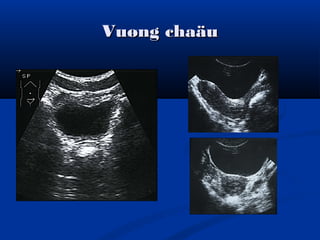

Vuøng chaäuVuøng chaäu

Khaûo saùt sieâu aâmKhaûo saùt sieâu aâm